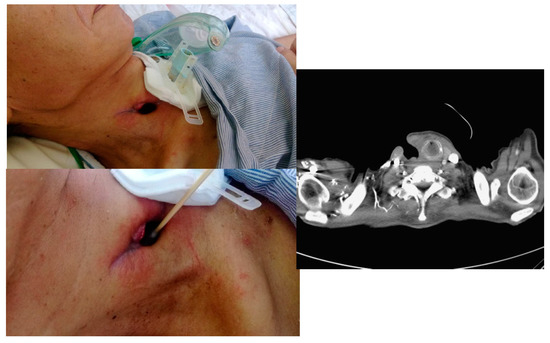

2.1. Case 1

2.2. Case 2